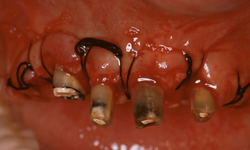

Prima

Caso clinico di recupero di radici mediante intervento chirurgico parodontale di allungamento di corona clinica, che ha permesso la realizzazione di una struttura atta alla stabilizzazione della protesi.